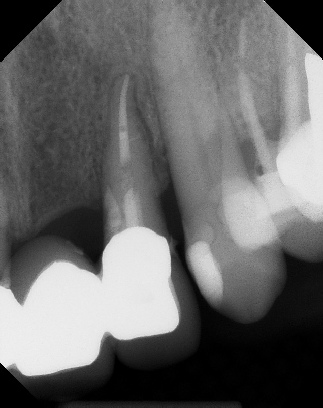

COMPLICATED ANATOMY LARGE LESIONS CALCIFIED CANALS PERFORATION / RESORPTION SEPARATED INSTRUMENTS SURGICAL CASES RETREATMENT / pOST REMOVAL OPEN APICES ACCESS THRU CROWNS Root Canal Case Portfolio